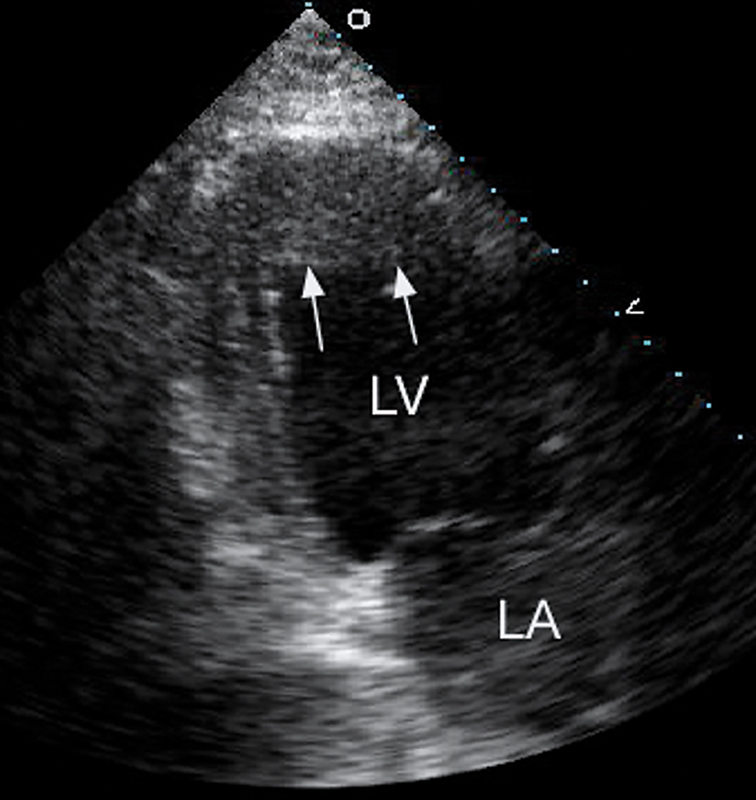

فحوصات تشخيصية لبعض امراض القلب والشرايين التاجية